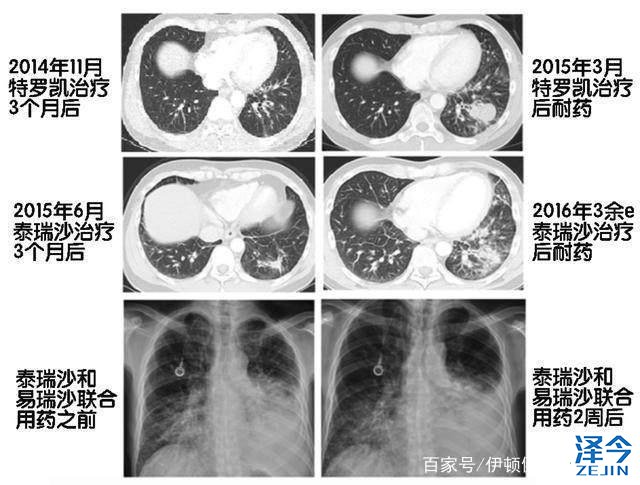

一位40多岁的非小细胞肺癌患者、2014年中旬就诊时发现在骨头和纵膈有转移灶,随后、基因检测验证患者EGFR基因的19号外显子存在缺失突变,患者遂服用特罗凯予以治疗,有效控制病情6个月后复发,活检中发现为T790M突变所致,改服泰瑞沙80毫克每日,病情稳定长达12个月后,患者因淋巴管炎症不得不转而使用卡铂和紫杉醇联合化疗,化疗至第四个疗程时,病情又有所进展,故而启用纳武单抗,单抗治疗四疗程后,因呼吸困难重做CT发现淋巴管炎加重,在脑、肝等处发现新转移病灶,由此开始使用培美曲塞化疗,然病情继续恶化。

最终、通过进行数字PCR检测发现了C797S基因突变,再次进行深度测序,发现T790M和C797S反式构型。于是、患者使用泰瑞沙(AZD9291)和易瑞沙的联合疗法,仅三天病症便有所好转,两周后咳嗽与呼吸困难得到控制,影像学检查也证实患者病情缓解,但至联合用药一个月后,病症重现、病情恶化,半月后患者离世。

患者影像学检查报告

该案例中患者使用泰瑞沙(AZD9291)联合易瑞沙后,总生存期仅为六周,通过对患者的两份血液样本分析,证实了患者携带的C797S癌细胞被联合用药方案予以压制,但在C797S突变丰度下降的同时,19del和T790M突变丰度却显著增加,从而导致了治疗的最终失败。